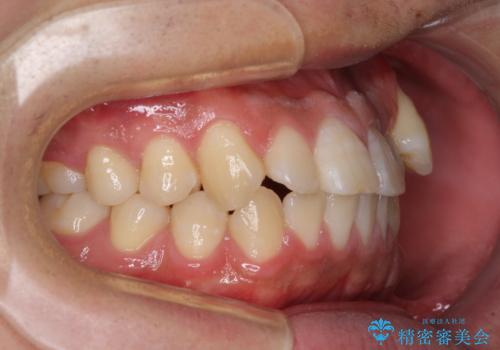

- 八重歯と前歯の隙間を気にして来院された患者様です。

八重歯の改善のため、奥歯を後方に移動させていくこととし、患者様と相談の上、ワイヤー装置にて矯正治療を行うこととしました。

舌突出癖が改善されず、なかなか正中の隙間や上下の前歯が接触しなかったために治療が長期化してしまいました。